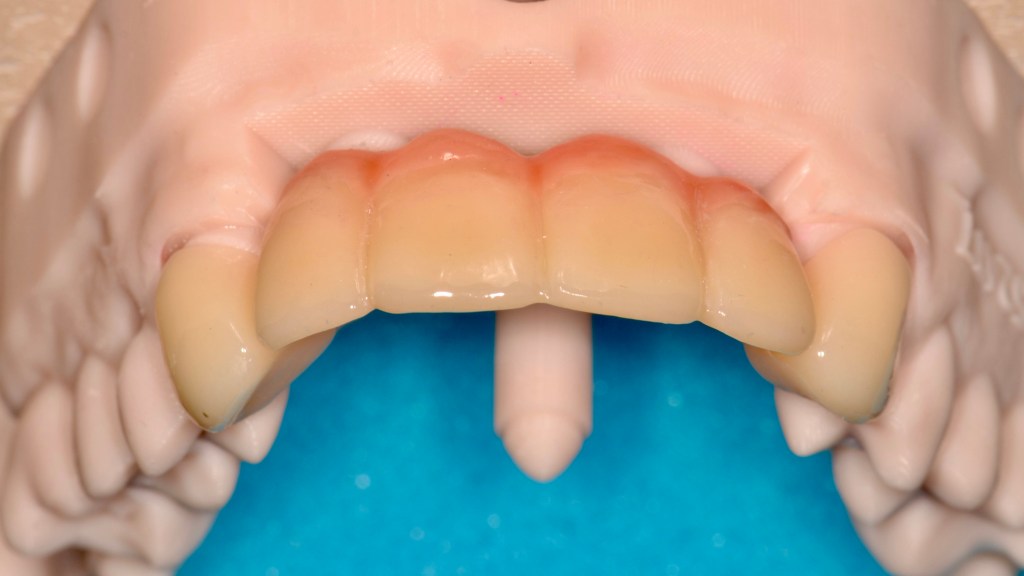

Ceramic Bridge